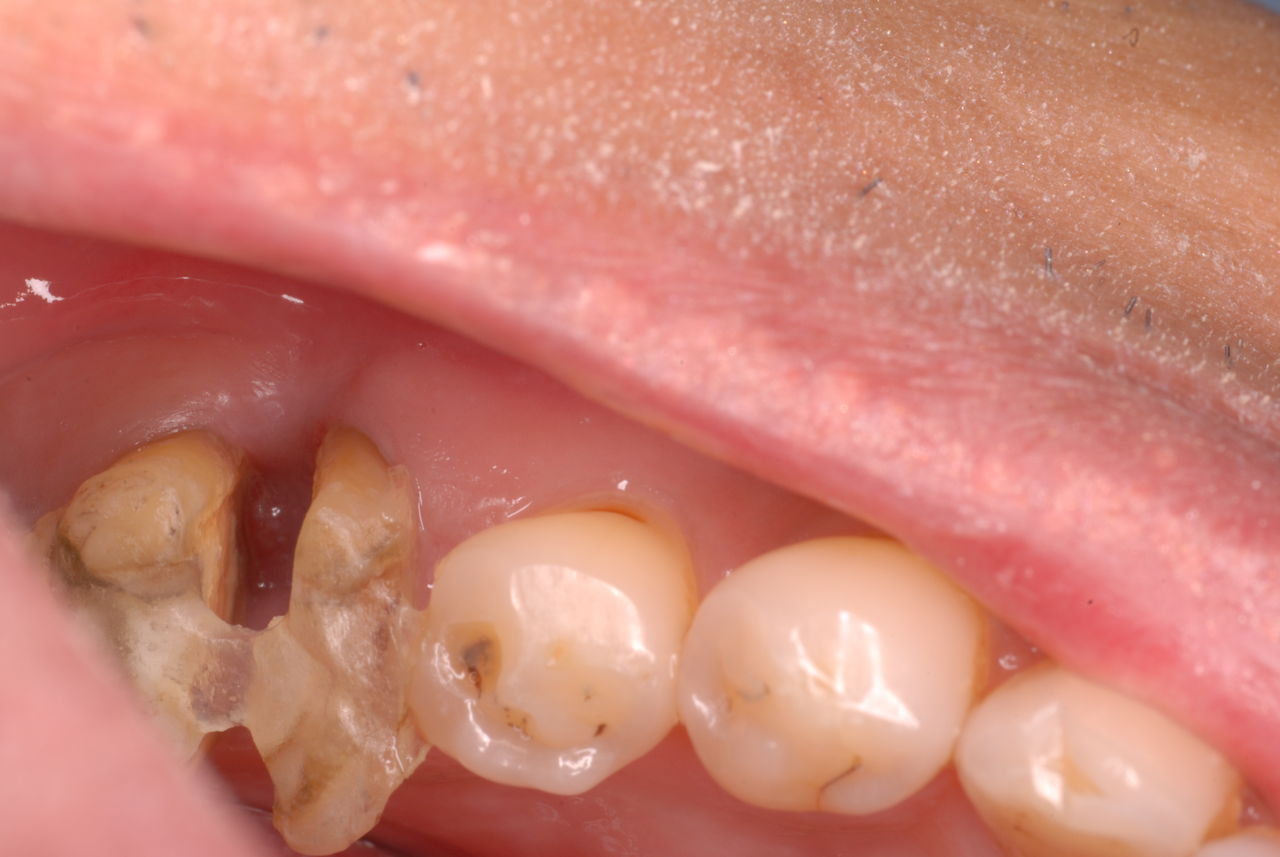

写真左下の親知らずが痛くなり抜歯しました。その後歯茎を除去して虫歯を露出させる処置を二回ほどしています。

レントゲンでは小さいですが、こう言う虫歯が一番怖いのです。

治療の成功率は極めて悪くすぐ再発しやすいのです。